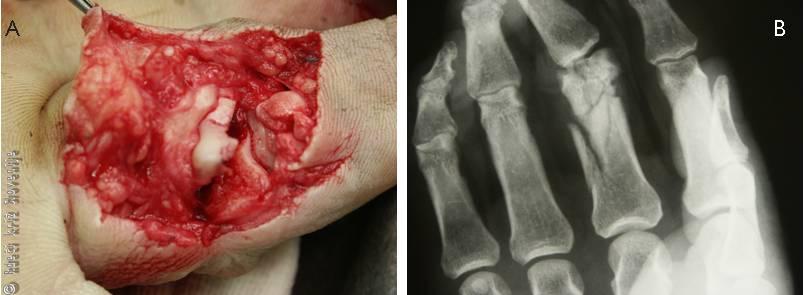

Slika 26

Odprt, zdrobljen sklepni zlom bližnjega členka sredinca med operacijo (A) ter na rentgenskem posnetku (B).

Zdravljenje zlomov členkov je konzervativno z različnimi načini imobilizacije po uravnavi zloma v prevodni anesteziji ali operacijsko. Pomembno je zgodnje razgibavanje, da ohranimo gibljivost sklepov. V primeru odprtih zlomov takojšnja učvrstitev okostja omogoči oskrbo mehkih tkiv.